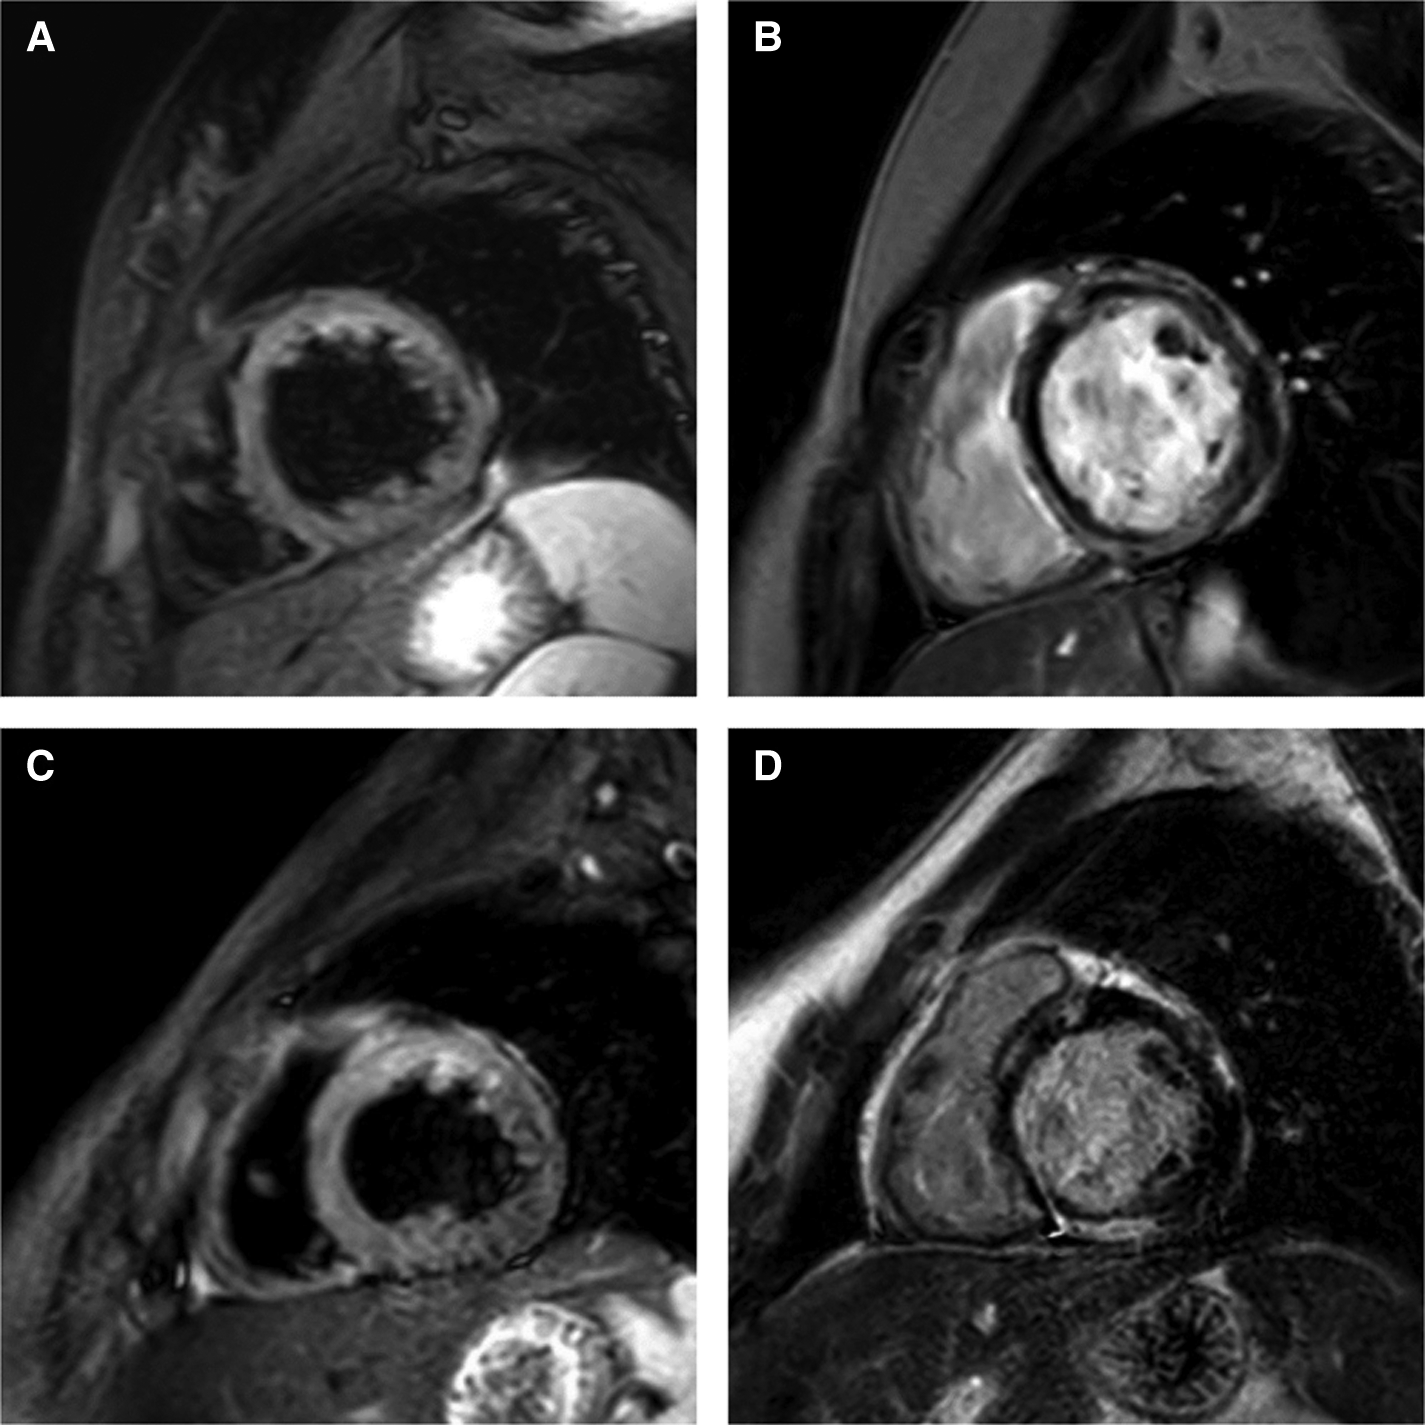

Electrocardiography revealed low voltage in the limb leads and premature ventricular contraction (Figure 1). There was no abnormal finding on the chest radiograph. Transthoracic echocardiography revealed left ventricular dilatation with a reduced ejection fraction of 45.1% (biplane Simpson's method). Ambulatory Holter monitoring exhibited repeated episodes of nonsustained polymorphic ventricular tachycardia. Cardiac magnetic resonance (CMR) imaging 2 days after presentation revealed global left ventricular dysfunction with an ejection fraction of 41%, marked hypokinesia, high T2 values in the apical to mid portion of the anterior wall, and diffuse multifocal patchy late gadolinium enhancement (LGE) (Figure 2).

Figure 2

Short-axis cardiac magnetic resonance imaging on days 2 (A,B) and 18 (C,D) after the patient's presentation. (A) High signal intensity in anterior wall of left ventricle on T2-weighted image. (B) Diffuse multifocal patchy late gadolinium enhancement (LGE). (C) Sustained high signal intensity in anterior wall of left ventricle on T2-weighted image. (D) Persistent multifocal patchy LGE.

The troponin I concentration peaked 2 days after presentation (0.689 ng/ml); subsequently, it gradually declined and reached its nadir 9 days after presentation (0.153 ng/ml). Thereafter, it resumed its rising trend, and the patient was administered 1 g/kg of pulsed methylprednisolone therapy for three consecutive days, followed by a planned oral prednisolone taper. CMR imaging 18 days after presentation continued to demonstrate high T2 values in the apical to mid portion of the anterior wall and a slightly decreased extent of diffuse multifocal patchy LGE. A right ventricular endomyocardial biopsy was performed to exclude other etiologies of myocarditis, including giant cell myocarditis. Histological examination of the biopsy specimen revealed focal myocardial degeneration and interstitial edema without significant inflammatory cell infiltration. The patient was discharged 31 days after presentation due to the reduced burden of ventricular tachycardia, improved symptoms, and partial recovery of ventricular function.

The heart function of the patient in this report was persistently impaired, and LGE was sustained on short-term follow-up CMR imaging. LGE was an independent predictor of mortality and major adverse cardiac events in adult patients with myocarditis (33, 34). The midwall septal pattern of LGE has been associated with late progressive deterioration of left ventricular function (35). Recent studies investigating changes in CMR imaging findings in patients with C-VAM have demonstrated sustained and decreased LGE on follow-up CMR imaging (13, 36, 37). Persistent LGE was observed in a considerable proportion of adult and pediatric patients with myocarditis on follow-up CMR imaging at 3–6 months, even after normalization of inflammatory and cardiac markers (38, 39). Although LGE without edema at 6-month follow-up CMR imaging was associated with a worse outcome in adult patients with acute myocarditis, the clinical significance of LGE and longitudinal changes in heart function in C-VAM require further investigation (40).